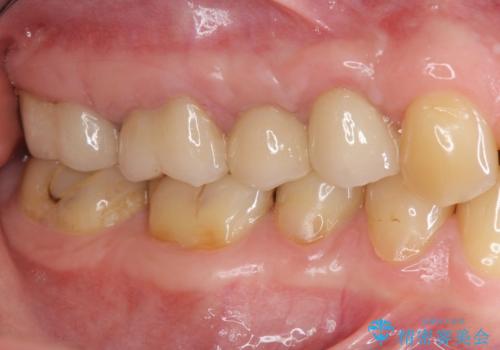

機能の回復・再感染の予防 →精密なジルコニアクラウンの作製

一つ一つの工程を丁寧に行うことで、根尖病変の改善傾向も見られ、安定した歯周環境を整えることができました。